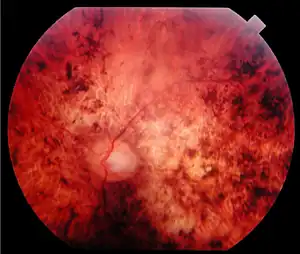

| Fundus of a 34-year-old patient with cone rod dystrophy due to Spinocerebellar Ataxia Type 7 (SCA7). Note that the macular area, and also the mid periphery, are atrophic. | |